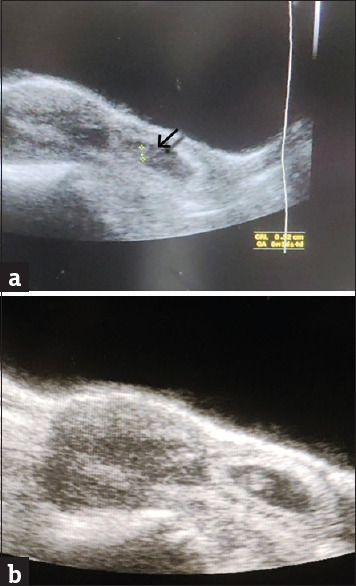

Cervical ectopic pregnancy (CEP) is a rare and challenging condition that requires prompt management to prevent complications. We present a case of a 27-year-old woman with a history of prior uterine surgeries who presented with vaginal spotting. Ultrasonography revealed an empty uterine cavity and a growing gestational sac with a viable foetus in the cervical canal. Despite methotrexate therapy, her beta-human chorionic gonadotropin hCG levels continued to rise, necessitating an alternative treatment approach. Bilateral uterine artery embolisation (UAE) was performed to reduce the risk of haemorrhage before hysteroscopic resection of the pregnancy. The combined approach of UAE and hysteroscopic resection successfully managed the CEP, leading to a favourable outcome. This case highlights the importance of early detection, tailored interventions and multidisciplinary collaboration in the management of CEP. UAE, in conjunction with hysteroscopic resection, offers a promising treatment option for CEP, minimising complications and preserving reproductive health.